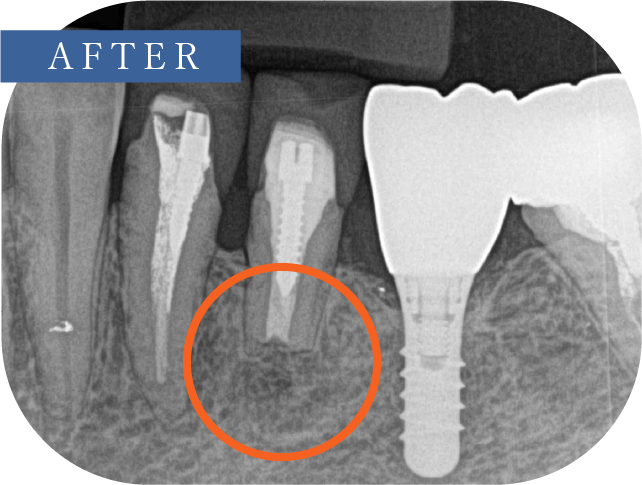

(根尖切除術・意図的再植術)